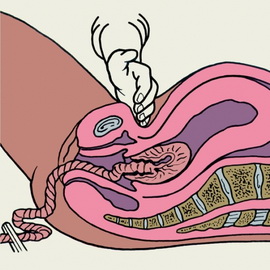

Послідовно період починається з народження дитини і закінчується вигнанням посліду.

Рот і ніс немовляти очищають від слизу, іноді його можуть потримати вниз головою, щоб видалити слиз з легких. Новонароджений робить свій перший вдих і видає свій перший крик: «Я народився!» Пуповину перерізають після закінчення пульсації пуповини судин. Весь цей час дитина лежить на животі або грудей матері, проводять його перше прикладання до грудей. Після перетину пуповини малюка передають неонатолога і медичній сестрі дитячого відділення. Кожен новонароджений на перших хвилинах життя оцінюється за шкалою Апгар.